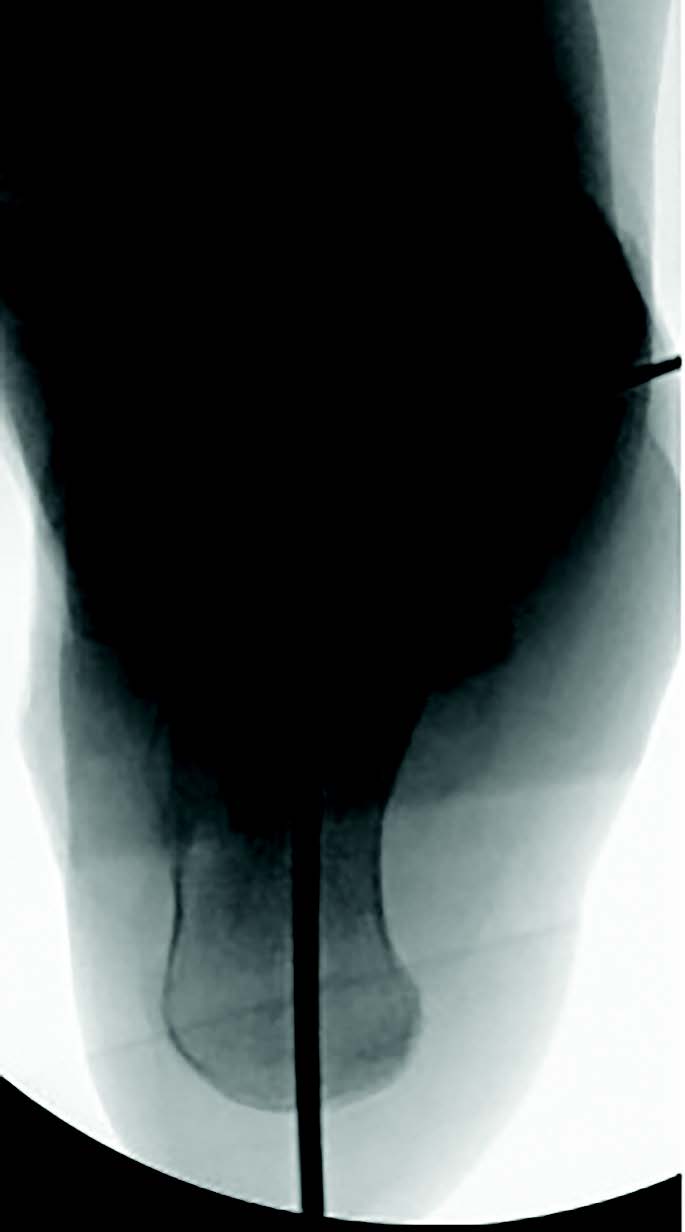

One can easily control field of view in standard X-ray imaging by adjusting the head tube aperture, but how does the surgeon or radiology tech control field of view when performing intraoperative C-arm imaging? Imaging the entire foot and ankle on one view can be challenging, even when using a large C-arm, which hinders intraoperative alignment assessment during reconstructive surgery. Here the surgeon can obtain maximum field of view by fully opening the tube head aperture and then placing the foot or ankle as close to the image intensifier as possible. In our experience, this will capture the greatest amount of the foot or ankle and will allot the surgeon the highest quality image possible (see images below).

Moving the head tube away from the body results in a narrow field of view, but the area of interest becomes magnified. Both of these maneuvers are useful depending on the circumstance, but the radiology tech will need guidance from the surgeon as to the preferred image. Most mini C-arm units have control settings that allow either magnification or a wider field of view, but the field of view will be smaller than when using a large C-arm if using the magnification setting. One should note that using the magnification setting will increase the radiation exposure; therefore, moving the body part closer to the intensifier is the ideal method.

These criteria should serve as a checklist intraoperatively to ensure obtainment of an appropriate simulated weight-bearing lateral radiograph. The plate position is at 90 degrees to the image intensifier, and the surgeon loads the foot using the palm the hand with the ankle dorsiflexed to 90 degrees and the toes pointed to the ceiling by internally rotating the knee. Once positioned, the image intensifier should move in as close as possible to the foot to capture the greatest area possible in one view.4

field of view (top). The bottom image

demonstrates internal knee rotation to

ensure a proper lateral view.